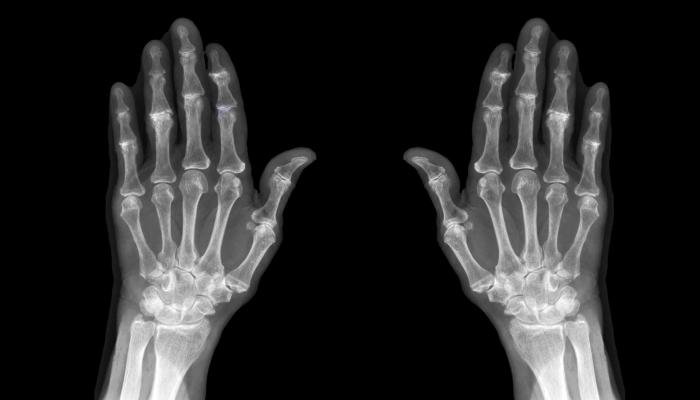

وأشار الباحثون، في نتائج الدراسة التي نُشرت في دورية “رعاية وأبحاث التهاب المفاصل”، إلى أنه على الرغم من أن هشاشة العظام يمكن أن تؤثر على اليدين والركبتين والوركين والعمود الفقري، فإن أولئك الذين يعانون من هذه الالتهابات في الركبة والورك أكثر عرضة للإصابة بمرض باركنسون من أولئك الذين يعانون من أشكال أخرى من المرض.

وأشارت الدراسة، التي فحصت بيانات ما يقرب من 67 ألف شخص بالغ في تايوان تتراوح أعمارهم بين 50 و64 على مدى أربع سنوات، إلى أن ما يقرب من نصف المشاركين يعانون من هشاشة العظام، والتي تحدث عندما يتآكل الغضروف الذي يغطي نهايات العظام عند المفاصل بمرور الوقت، في حين أن النصف الآخر لم يكن يعاني من هذه الحالة.

وأظهرت البيانات أن المشاركين الذين يعانون من التهاب مفاصل الركبة والورك معرضون لخطر الإصابة بمرض باركنسون بنسبة 55٪، وهو اضطراب دماغي يسبب الاهتزاز والتصلب وصعوبة المشي والتوازن والتنسيق في الحركة، فيما كان الأشخاص المصابون بهشاشة العظام الذي يصيب المفاصل الأخرى أكثر عرضة للإصابة بباركنسون بنسبة تتراوح بين 30٪ و 40٪.